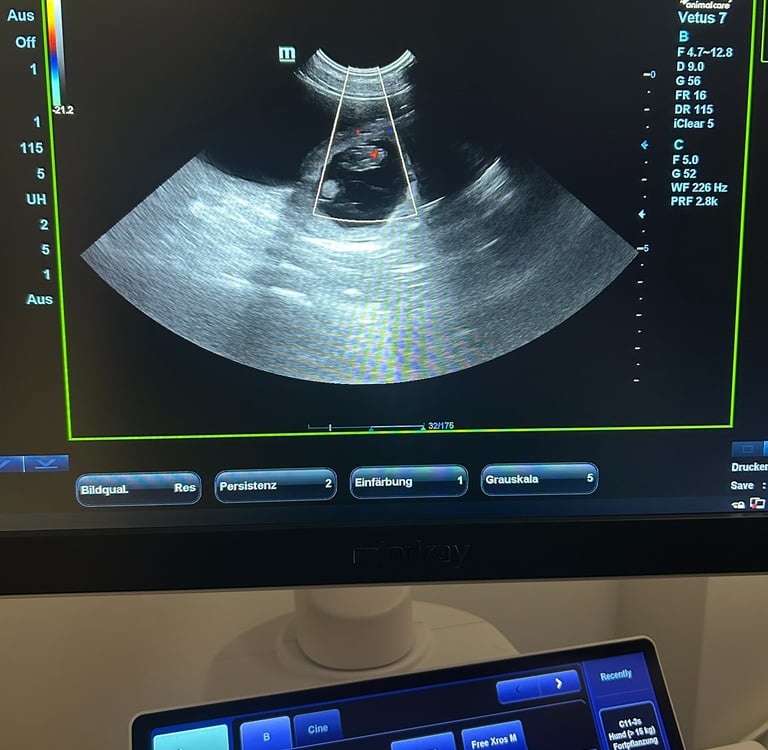

Alma ist trächtig!

3/13/2025

Heute waren wir mit Alma beim Tierarzt. Die Bilder im Ultraschall zeigen mehrere kleine Welpen. Wir freuen uns riesig und erwarten in der Osterwoche Almas Nachwuchs.